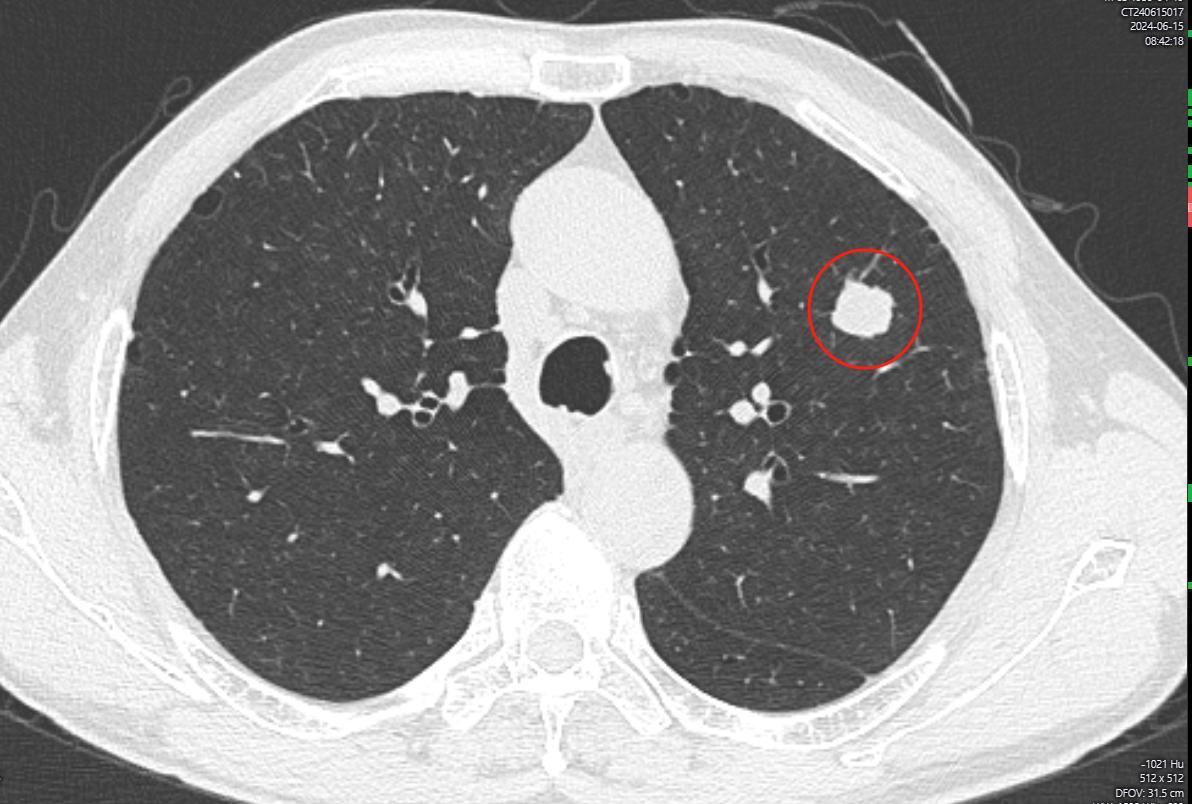

体检发现肺结节,恶性程度很高:大细胞合并小细胞肺癌

近日,一则关于“体检发现肺结节,恶性程度很高:大细胞合并小细胞肺癌”的新闻引发关注。这种罕见的肺癌类型不仅对患者构成巨大威胁,也给医疗系统带来了严峻挑战。

对医疗系统而言,这种混合型肺癌的诊断和治疗都面临着巨大挑战。首先,传统的影像学检查往往难以区分这种混合型肺癌与其他类型的肺癌。其次,由于病例较少,缺乏统一的诊疗指南,医生在制定治疗方案时往往需要结合多种因素进行个体化决策。